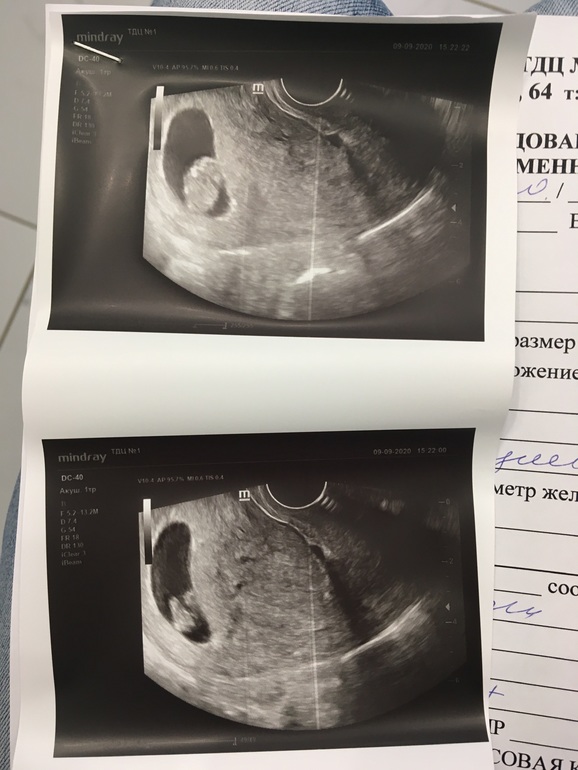

Ахах) Я тоже так сходила в 10 недель на неудачное узи. В чате все девочки выкладывали классные снимки со своими креветочками (как они их называли), там видно было и ручки и ножки. А мне дали смазанный снимок и там вообще ничего непонятно! Я пишу, почему у всех креветочки, а у меня колобок какой-то?) Но видимо вертелся, не хотел сниматься. Даже на экране ничего непонятно было плюс ещё и тонус сжал пя.

Вот что это? Яйцо в яйце, блин! Вышла расстроенная, думаю зачем столько денег отдала. Не могла даже срок высчитать долго🤦♀️

А у меня на 12 спинкой лежал маленький кабачок😅 выросла вполне приличная барышня - стесняется и закрывает личико ручками😍